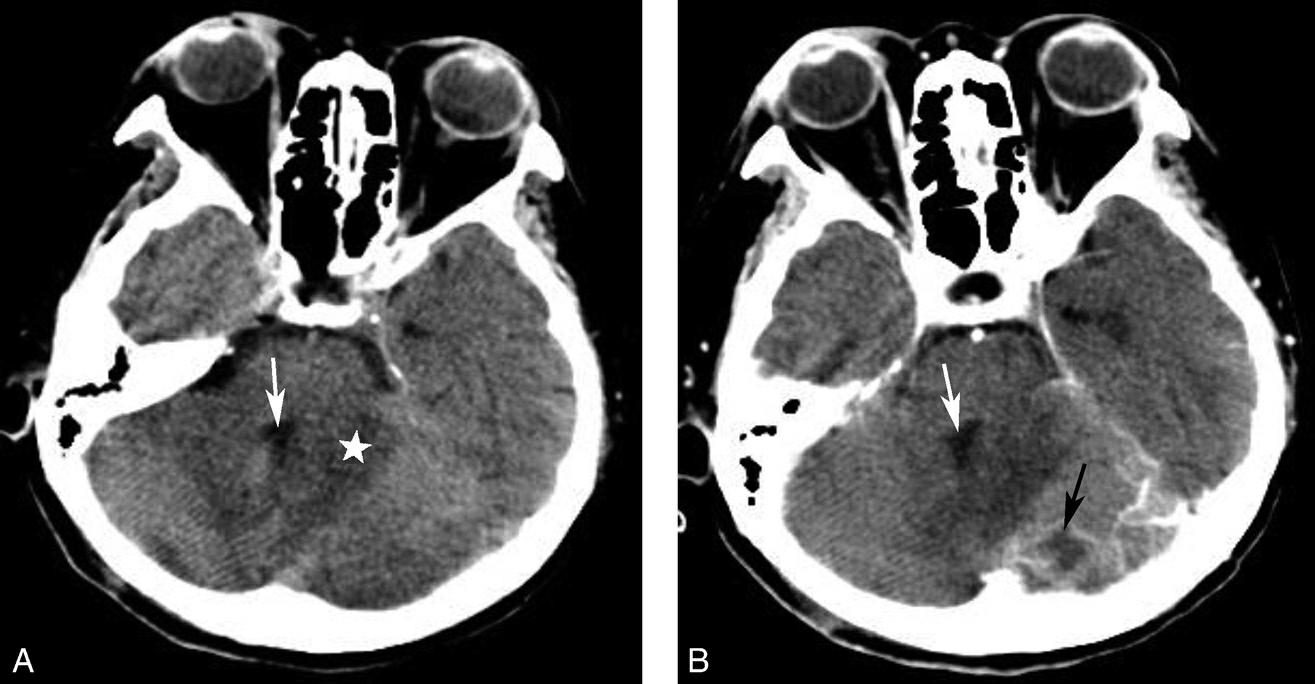

破裂孔、卵圆孔、棘孔及斜坡等均为重要的解剖结构,临床常见疾病如鼻咽癌常侵犯上述结构(图1-2-3)。颈静脉孔区较常见的肿瘤为颈静脉球瘤,常伴有颈静脉孔及其邻近骨质的破坏(图1-2-4)。

图1-2-3 鼻咽癌颅底骨质破坏

A.横断面;B.横断面(骨窗)

骨窗示左侧岩尖、斜坡、左侧蝶骨大翼骨质破坏、受侵(白箭),肿瘤经破裂孔侵入颅内(黑箭头)

图1-2-4 右侧颈静脉球瘤

A.横断面(骨窗);B.横断面

右侧颈静脉孔区不规则骨质破坏(箭),局部见软组织肿块(☆)